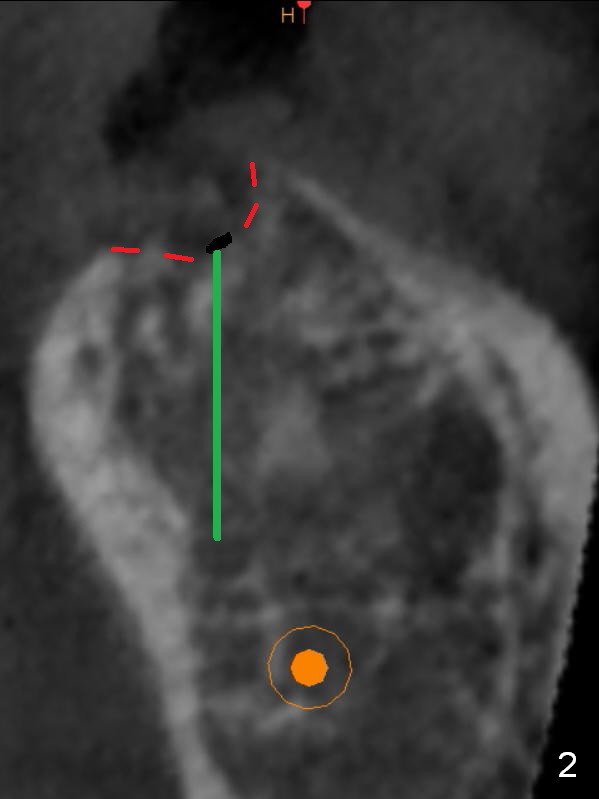

Preop palpation of the edentulous area at #18 does not show the flatness of the ridge top as shown by CBCT. Incision reveals that the ridge is not as wide as CBCT indicates (Fig.1 (coronal section) between arrowheads). In fact the ridge is concave (Fig.2 red dashed line). Osteotomy is initiated in the middle of the concavity (Fig.2 green line) with insertion of 7 mm guide pin (Fig.3). After removal of the pin, the osteotomy is moved buccally (Fig.4). After Marking Bur and 4.3 mm Magic Drill, a 5x9 mm IBS implant is placed with 2.8 mm clearance from the Inferior Alveolar Canal (Fig.6). Following deepening the osteotomy with Final Drill, the implant is placed deeper (Fig.7). The osteotomy happens to be established in the mesial socket, since the distal socket has not completely healed (Fig.6 yellow dashed line). Granulation tissue is removed. Since the lingual crest is lower than the buccal one (Fig.1 B), there is lingual thread exposure after implant placement (Fig.5). The exposed thread is covered by bone graft (autogenous bone, allograft and Osteogen, Fig.5 pink circles). Some of the graft is apparently pushed into the distal socket (Fig.7 yellow dashed line) post GBR and suture. As the implant is placed twice, insertion torque is <10 Ncm (although the implant is stable). A 5x3 mm healing abutment is placed (Fig.7 H).